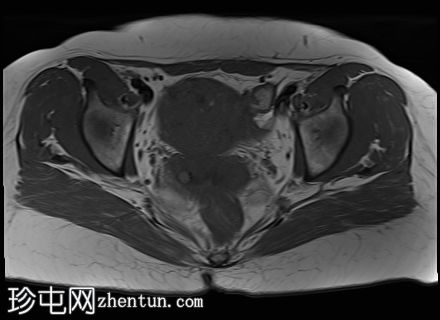

冠状位

T2加权像

子宫前壁交界区局灶性增厚,边界不清。形成直径约3厘米的局灶性肿块样病变,轻度压迫膀胱。肿块边界模糊不清,可见多个细小出血灶,在T1加权像和T2加权像上均呈高信号,提示局灶性子宫腺肌症。

子宫体前壁可见另一处病灶,位于上述病灶尾侧,边界清晰(有包膜)。该病灶在T1和T2加权像上均呈低信号,内部未见异常信号灶,周围可见少量明显血管通道,提示为小型子宫肌瘤。

边界模糊不清是局灶性子宫腺肌症(无包膜)的特征。此外,病灶内存在多个微小的内部出血灶(异位腺体),且邻近增厚模糊的交界区,这些都是局灶性子宫腺肌症的诊断标准。

在上述病灶尾侧可见另一处具有不同影像学特征的病灶,该病灶边界清晰(有包膜),且信号均匀(无微小的内部出血灶),提示可能合并子宫肌瘤。

子宫腺肌症通常累及范围较广,累及子宫的大部分区域(通常为后壁),但宫颈通常不受累。尽管子宫常明显增大,但其整体轮廓通常保持完整。

在某些情况下,子宫腺肌症也可能局限于子宫,形成肿块。在这种情况下,可以使用“腺肌瘤”一词,尽管对于“局灶性腺肌症”和“腺肌瘤”是否指同一种疾病,目前似乎存在一些争议。